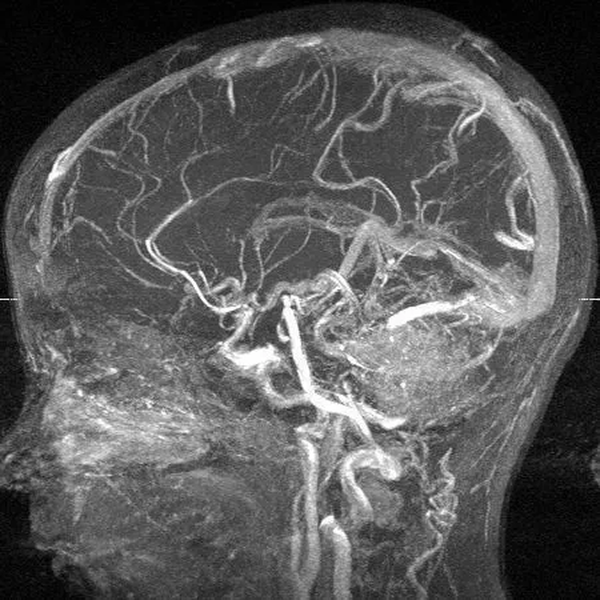

МР-ангиография головного мозга

Магнитно-резонансная томография – высокотехнологичный и безопасный метод диагностики. МРТ головного мозга позволяет определить причину неврологической патологии, в том числе сосудистого происхождения при выполнении МР-ангиографии. В основе метода лежит использование магнитного поля. Последнее возбуждает протоны водорода, которых больше всего в насыщенных водой тканях. Обратный сигнал улавливается датчиками, программа обрабатывает показатели, а врач получает изображение.

Шаг снимков начинается от 1 мм. Тонкие срезы позволяют сделать результат достоверным и информативным. При изучении мозга могут применять МР-ангиографию с контрастом. Проведение усиленного сканирования сосудов даст информацию о наличии:

- стеноза;

- васкулита;

- аневризмы и расслоения артериальной стенки;

- артериовенозной мальформации и др.

МРТ прекрасно показала себя при всестороннем исследовании внутримозговых нарушений, обнаружении всевозможных новообразований головы пациента. Когда делают МРТ шейного отдела позвоночника или головы устанавливается специальная катушка, позволяющая усилить эффективность изображения.

Итогом диагностики является трехмерное изображение, которое способно помочь лечащему доктору установить верный диагноз.